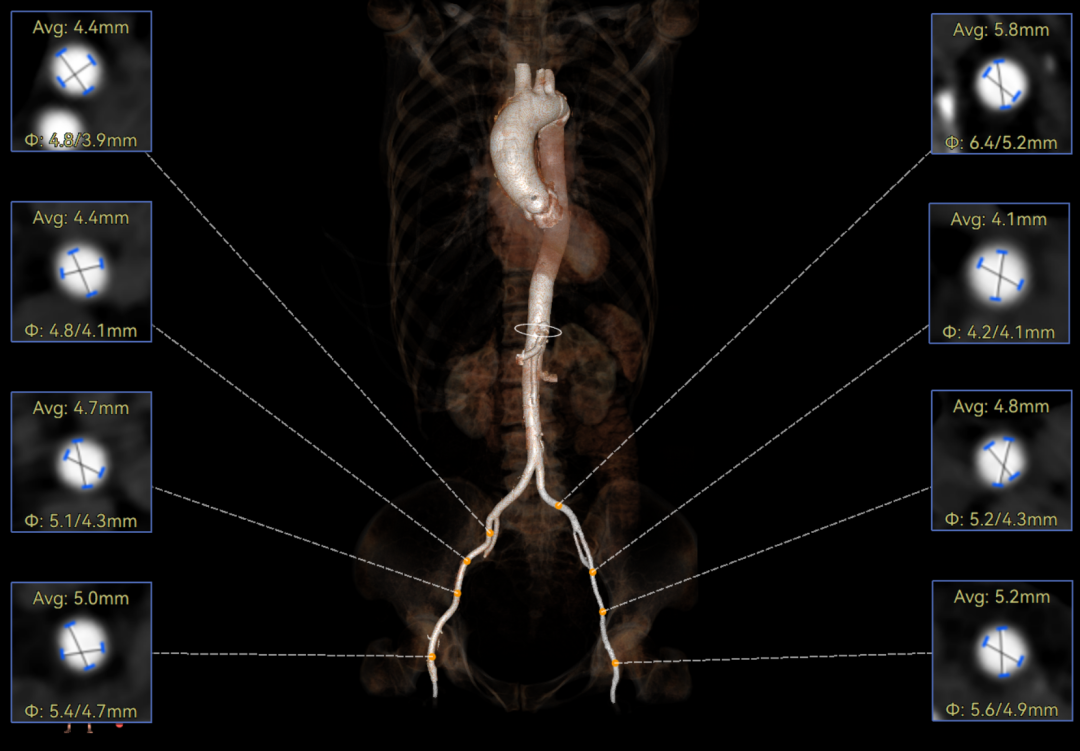

CT报告提示

主动脉瓣环周长径21.4mm,小瓣环,LVOT直筒型结构;风湿性三叶瓣,三窦交界粘连,限制最窄预估周长17.5mm。心脏角度41.8,瓣上限制重,无冠脉风险。

外周入路无明显迂曲,胸腹主散在钙化。双侧股动脉内径小,右股最窄4.4mm,左股最窄4.1mm,需使用内联鞘版本尝试通过,右股中分叉。主动脉弓角、弓距可。